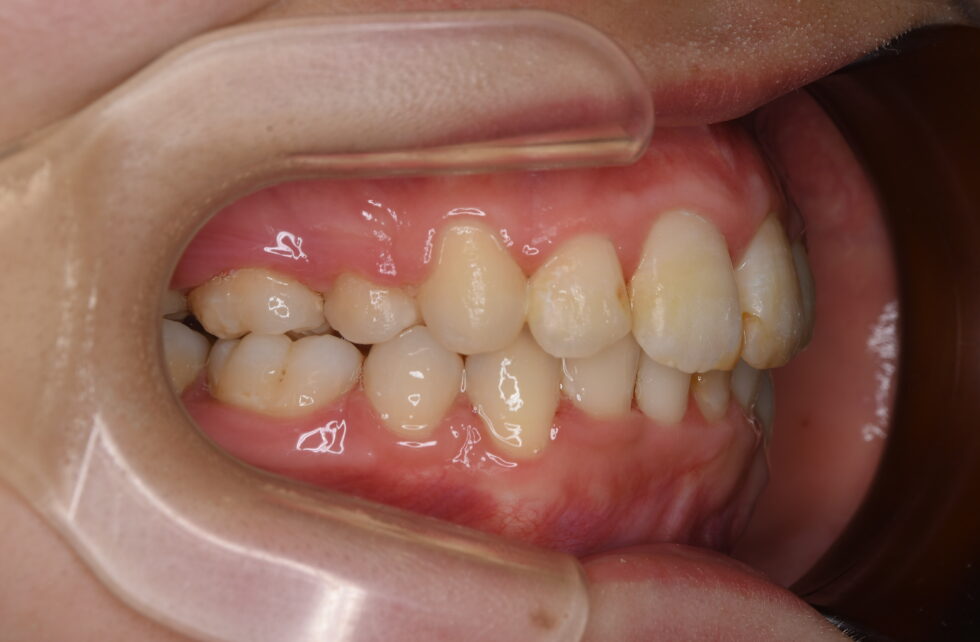

初診時年齢18歳の女性。叢生を伴う上顎前突のケース。

前歯の突出と乱れを気にしておられました。マルチブラケット装置を使用して、上下顎左右側小臼歯の抜歯による動的治療を行いました。突出していた前歯を後退し、乱れも改善することが出来ました。動的治療期間は2年10ヶ月間